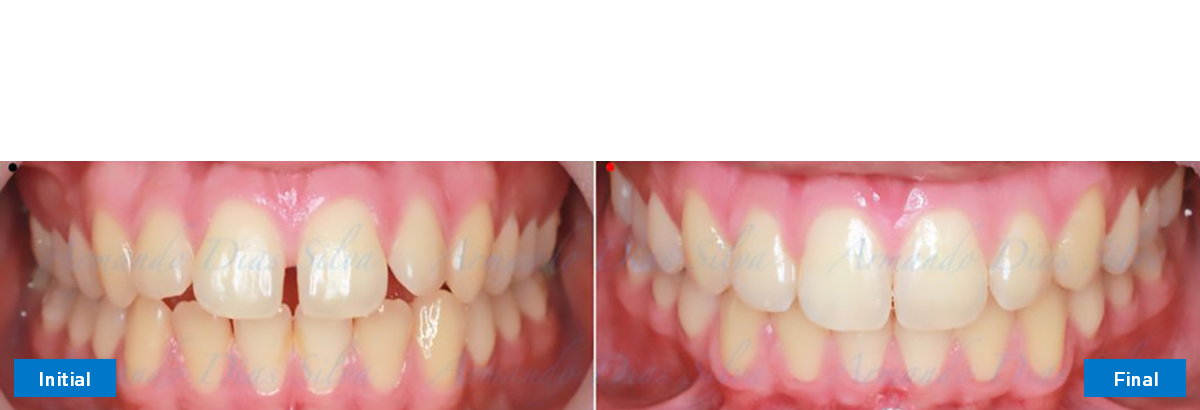

Principal queja del paciente: Protrusión del incisivo central y mordida abierta. El paciente rechaza la expansión del arco palatino (MARPE) y las extracciones.

Este paciente adolescente presenta molares de Clase II y no le gusta su mordida abierta ni lo protrusivos que son sus dientes frontales. Por sus fotografías faciales, parece que su mandíbula es retrognática o le falta volumen en la barbilla. El historial del paciente también indica que existe un problema funcional al no haber guía de los incisivos.

• Diastema

• Incisivos superiores e inferiores proclinados

Se logran todos los objetivos principales:

• Molares de clase I logrados con distalización y sin elásticos

• Sin expansión maxilar, respetando la envoltura periodontal

• Incisivos inferiores retroinclinados, que mejoran la estabilidad a largo plazo